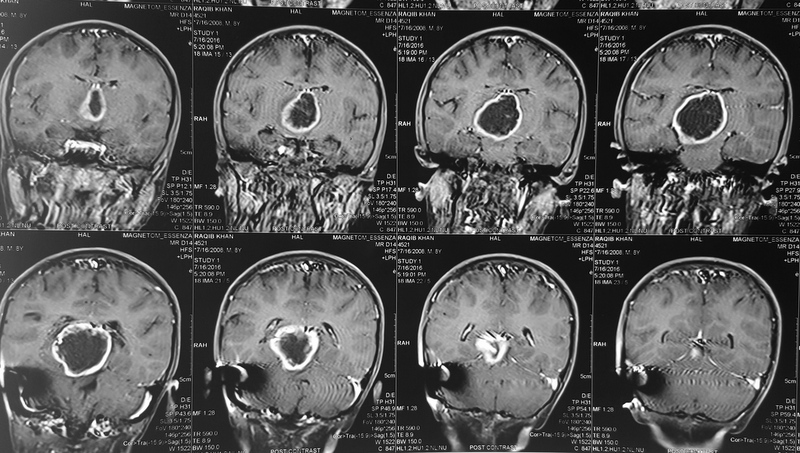

Pilocytic astrocytoma of Posterior Third Ventricle

A 9-year-old male child was evaluated for recurring headaches. Clinically, he had papilloedema. Imaging studies (Figs 1 to 3a & b) showed large posterior third ventricular tumor exhibiting peripheral rim contrast enhancement. The tumour was excised under general anaesthesia, in sitting position, by Supracerebellar Infratentorial approach. The tumour could be excised completely. He has been followed up, and MRI after three years showed only postoperative changes and no tumour residue (Figs 4a & b).

Fig 2a

(Fig 2a)

Fig 2b

(Fig 2b)

Fig 3a

(Fig 3a)

Fig 3b

(Fig 3b)